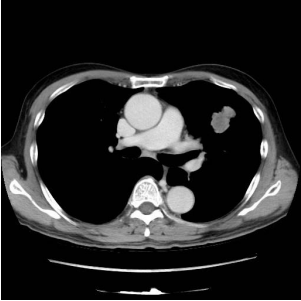

17. 63歲女性病人因風濕性心臟病換過二尖瓣瓣膜,心律不整長期使用藥物。因為喘的情形加劇,CXR及電腦斷層如圖示,下列何者為是? (A) 為典型的 Interstitial Lung Disease,可以是idiopathic pulmonary fibrosis。 (B) 肺部有許多小點,Miliary TB無法排除。 (C) X光及電腦斷層有許多的線條,可以是kerley line 應為肺水腫。 (D) 無顯影劑肝臟卻明顯較亮要考慮Amiodarone 造成的 Interstitial Lung Disease。 (E) 有許多的點跟線,應考慮肺癌合併 lymphangitis carcinomatosis。